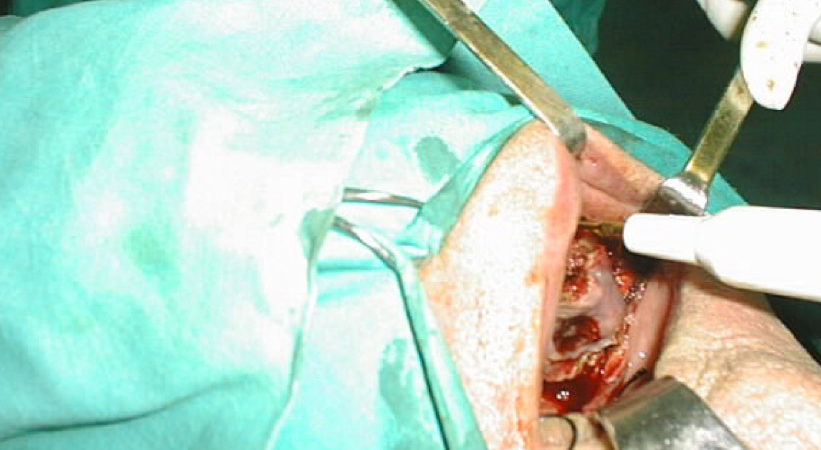

CASO CLINICO N° 3

Paziente di 92 anni portatore di un carcinoma squamoso dell’emipalato duro di sx infiltrante il seno mascellare omolaterale T4N1. È stata effettuata una maxillectomia parziale con dissezione conservativa del collo.

Tutti i pazienti operati hanno ben sopportato l’intervento, non si sono verificate nè emorragie nè infezioni post-operatorie e la degenza è stata di breve durata; tutti i pazienti hanno conseguito un buon risultato estetico e funzionale. La chirurgia piezoelettrica infatti causa un trauma minimo sull’osso con scarso sanguinamento permettendo una guarigione più rapida dei tessuti. Riteniamo che questa tecnica in determinati casi selezionati, soprattutto in pazienti di età avanzata, possa costituire una valida alternativa alla chirurgia tradizaionale.